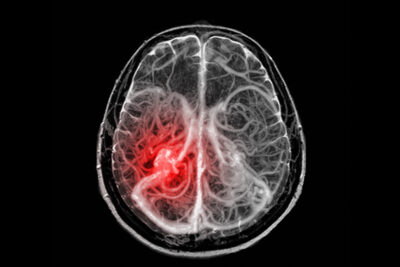

Thrombectomy for Basilar Artery Occlusion

For at least the past 25 years, mechanical thrombectomy has been tried to treat acute ischemic stroke caused by large vessel occlusions (LVOs). However, it was not until 2015 that multiple landmark trials finally proved what long had been presumed — endovascular therapy (EVT) is superior compared to best medical management. The 2015 studies investigated the most common type of LVO, a clot affecting the anterior circulation — distal internal carotid (ICA) or middle cerebral artery (MCA). Other LVOs, most notably basilar artery occlusions (BAOs), continued to be treated with EVT as well, but there was an absence of randomized trial data to support this practice.

Two studies published in 2023, ATTENTION (Endovascular Treatment for Acute Basilar-Artery Occlusion) and BAOCHE (Basilar Artery Occlusion Chinese Endovascular Trial), both performed in China, established, at long last, a benefit for EVT in BAO. These studies differed in their time windows (many more patients in ATTENTION were treated early — less than 12 hours) but were closely matched in their results. EVT nearly doubled the likelihood of a favorable outcome, increasing from 23% or 24% to 46%.